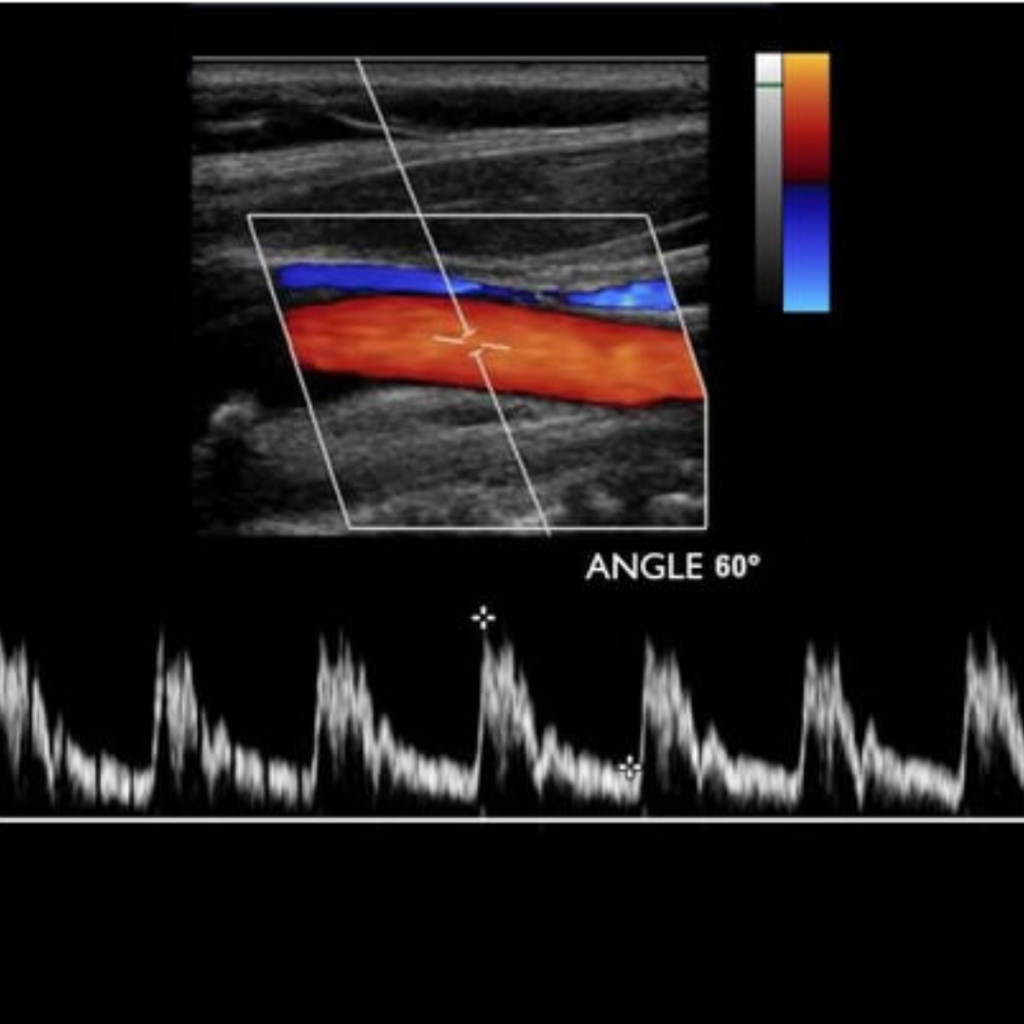

Уромед эмнэлгийн мэдрэлийн кабинет нь БНСУ-ын 2025 онд үйлдвэрлэсэн орчин үеийн шилдэг Samsung Medison V6 загварын хиймэл оюун ухаан дээр суурилсан аппаратаар тархины судасны өнгөт хэт авиан Допплер-Дуплекс шинжилгээг хийдэг.

тархины судасны өнгөт хэт авиан Допплер-Дуплекс шинжилгээгээр

Тархины судасны цусны урсгалын хурд, хөдлөл зүй

Хиймэл оюун ухаан дээр суурилсан автомат хэмжилтээр маш өндөр түвшинд нарийвчлан дүрслэн харж үүссэн судасны атеросклерозын товруу, эмгэгийг хэмжиж, судасны нарийслын хувийг тогтоож, бөглөрөл буй эсэхийг шууд харж оношлогоо хийдгээрээ маш давуу талтай.

Тархины судасны өнгөт хэт авиан дуплекссонографи шинжилгээ нь тархины судасны өвчнүүд, тархины цус хомсрох харвалт, шигдээс үүсэхээс урьдчилан сэргийлэх, эрт илрүүлэх, оношлоход чухал ач холбогдолтой дүрс оношилгооны бусад аргуудтай харьцуулахад харьцангуй өртөг багатай, цаг хугацаа хэмнэсэн инвазив бус шинжилгээний арга юм.